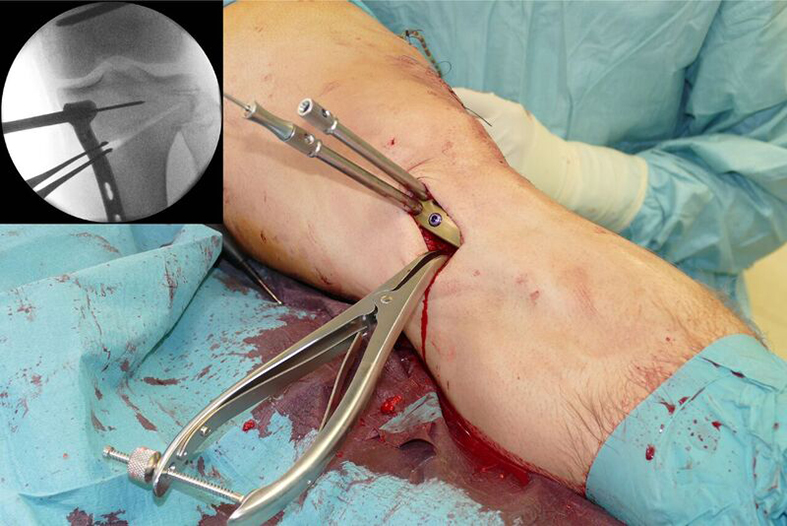

Following completion of the DFO and fixation with the TomoFix MDF Anatomical (Fig 10) the new aiming arm and K-wire guide system was used for the open wedge HTO.

After performing a minimally invasive approach at the medial proximal tibia, the first step of the new K-wire guiding system is definition of the hinge point with a K-wire from the lateral aspect (Fig 11). The guiding arm for the osteotomy was then inserted with the radiolucent hook in situ (Fig 12). The guiding arm should be adjusted under intensifier control and finally fixed with a K-wire. At this stage two K-wires for the osteotomy can be inserted and the guiding arm can be removed. The saw guide is then mounted and guides the sawblade safely (Fig 13 and 14).